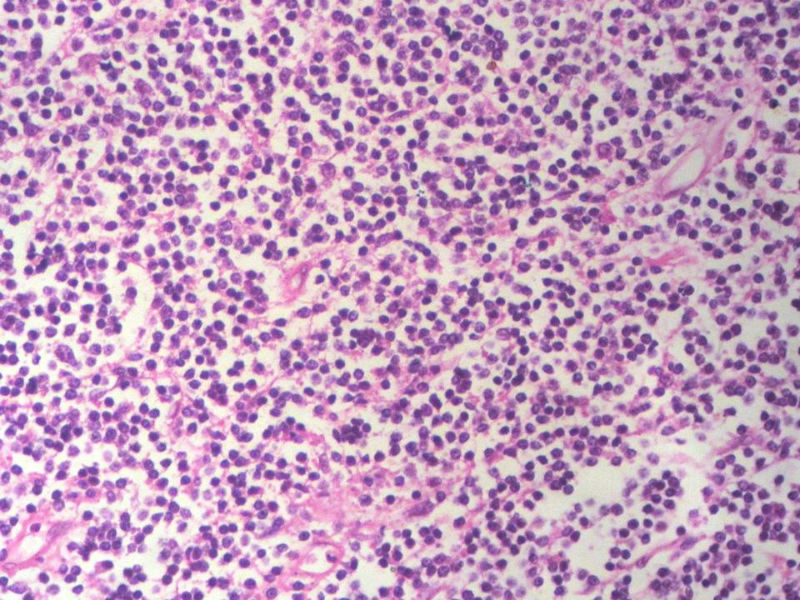

男,49岁,左眼睑球结膜下肿物2个月,手术切除。检查肿块3X2X2厘米,切面灰红色,质软。

淋巴样细胞。细胞形态单一,细胞小。主要鉴别:

1)粘膜相关淋巴组织淋巴瘤

2)小细胞性淋巴瘤/慢性淋巴细胞性白血病

3)套细胞淋巴瘤

形态结构与细胞大小,似不支持滤泡性淋巴瘤。

要多取材,标记鉴别假性淋巴瘤。